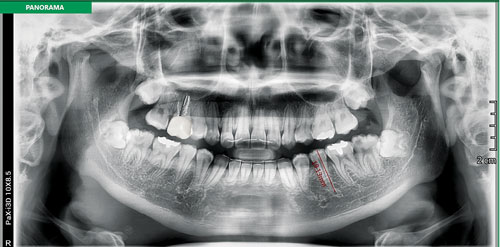

Рис.2 Ортопантомограмма с функцией Magic Pan от Vatech

Программные обеспечения легко интерпретируют клинический случай, а также за один оборот конического луча в 360 проекциях, дают возможность получить 2 изображения - ортопантомографию с функцией Magic Pan (Рис.2) и 3D реконструкцию объекта исследования. EzDent-i - прикладная программа, рассчитанная для работы с двухплоскостным изображением. Программное приложение оснащено различными макетами для удобства интерпретации клинического случая.